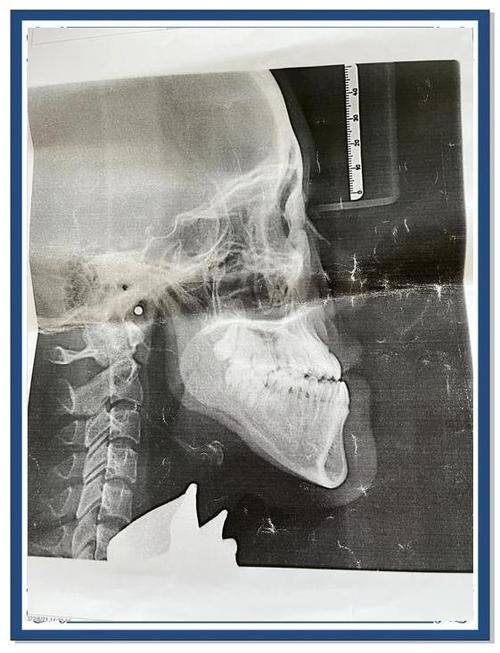

1. 精细诊断:韩相百医生在治疗前会进行全方面而细致的检查,包括口腔检查、影像学检查等。他能够正确地判断患者的牙齿和颌面问题,找出问题的根源。通过精细的诊断,他能够为患者制定出更适合的治疗方案,提高治疗的成功几率。